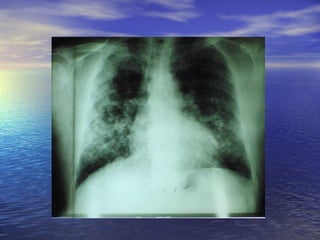

– Tele de torax (gran ayuda): Silicosis→opacidades

redondeadas campos superiores y medios.

Asbestosis→opacidades lineales irregulares basales,

fibrosis intersticial “panal de abeja”

•   Rx torax: formas simples→nodulos redondeados

densos 1.5-10 mm en campos pulmonares

superiores. Formas complicadas: lesiones >10

mm en uno a dos tercios del pulmon.

Calcificacion de ganglios en “cascara de huevo”

(5%)

Diagnóstico – Historia laboral(mas importante): disnea tardio y poco especifico Asbestosis→crepitantes basales y acropaquias – Tele de torax (gran ayuda): Silicosis→opacidades redondeadas campos superiores y medios. Asbestosis→opacidades lineales irregulares basales, fibrosis intersticial “panal de abeja” – Exploracion funcional respiratoria (valorar posible incapacidad): Asbestosis altera precozmente y Silicosis tardiamente. Patron restrictivo